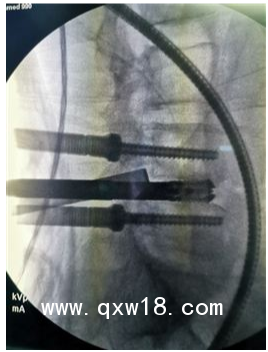

UBE技術(shù)即單側(cè)雙通道內(nèi)鏡技術(shù)(Unilateral Biportal Endoscopy Technique),適用于頸椎、胸椎、腰椎的退行性病變。與椎間孔鏡的單通道不同,該技術(shù)通常建立兩個通道,一個為觀察通道,一個為器械操作通道。觀察通道一般會用到0°或30°UBE內(nèi)鏡,操作通道使用UBE專器械,如UBE刮匙、磨鉆(UBE內(nèi)鏡磨頭)、UBE內(nèi)鏡刨刀、UBE內(nèi)鏡消融電極、UBE椎板咬骨鉗、UBE髓核鉗、UBE神經(jīng)拉鉤等。UBE技術(shù)的專用器械包,通過UBE技術(shù)還可以完成鏡下融合手術(shù)。

該技術(shù)開展脊柱手術(shù)時,克服了中心管狹窄、側(cè)管狹窄和椎間孔狹窄的局限。手術(shù)入路角度范圍廣,在不損傷脊柱結(jié)構(gòu)完整性的前提下,有效地對椎管進行了周向和局部減壓,保留了肌肉韌帶附著通過肌間間隙,保護背支內(nèi)側(cè)支,從而防止?fàn)繌垞p傷。這種內(nèi)窺鏡入路允許從對側(cè)后入路和孔外入路(椎旁孔外入路)進入孔,為治療所有類型的狹窄提供了靈活性,因此,UBE技術(shù)作為一種微創(chuàng)的融合方法,具有極強的實用性。

1、UBE內(nèi)鏡直徑小,操作空間大,移動范圍廣;

2、應(yīng)用傳統(tǒng)脊柱外科器械即可,不受特殊器械限制,普通尺寸器械處理增生退變組織效率更高;

3、比孔鏡更容易處理狹窄病例;

4、水介質(zhì)中操作,視野更加清晰,特殊器械可保持順暢出水;

5、熟悉的后方入路,學(xué)習(xí)曲線低;

6、適應(yīng)癥廣泛,能輕松完成鏡下融合、頸椎、胸椎、腰椎等復(fù)雜病例。